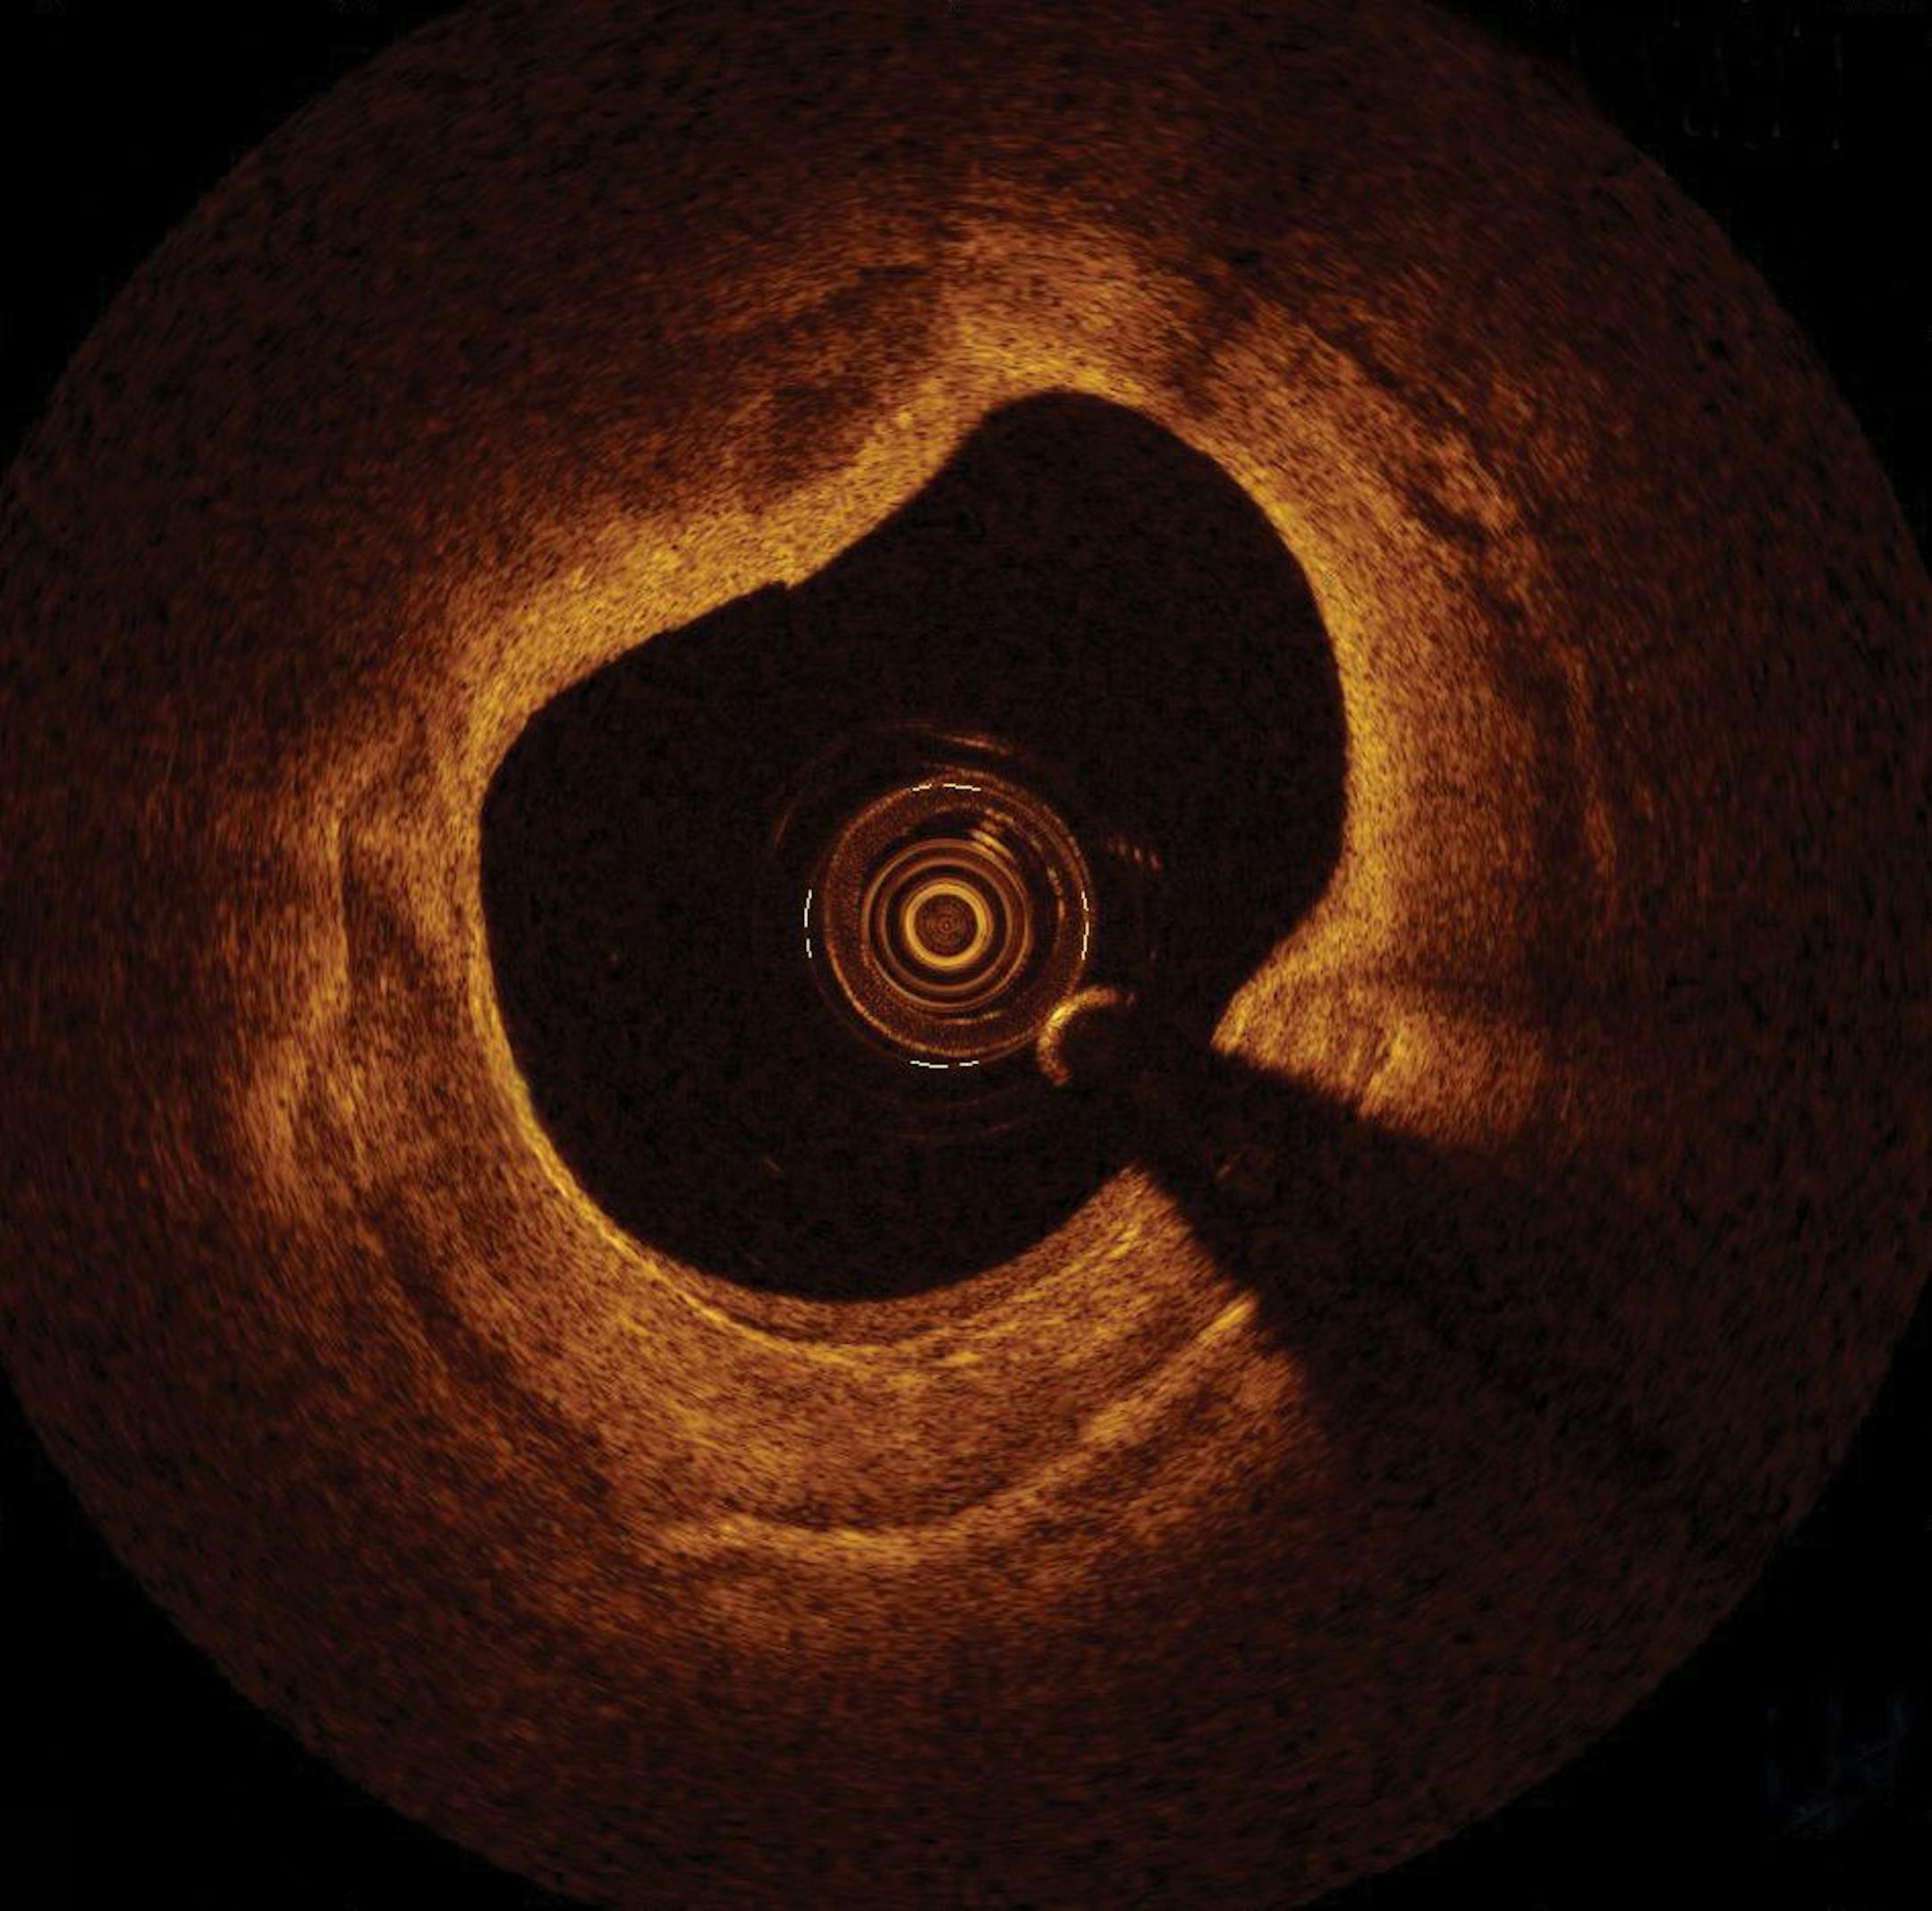

The images transmitted by the Ilumien PCI Optimization System allow physicians to view the inside of a blood vessel.

Ilumien pairs what is called fractional flow reserve (FFR), which measures pressure in an artery to find possible blockages, with infrared imaging called optical coherence tomography (OCT). The imaging technology is like a "high-definition television" compared with traditional ultrasound imaging that he has used for years, Chambers said. He is among the first physicians in the country to use Ilumien, which was approved by the U.S. Food and Drug Administration several months ago.

The Ilumien system combines those blood flow measurements with scanning that lets doctors actually see inside the blood vessel and measure the size of the blockage to better guide stent selection and placement. The OCT also helps doctors see if the procedure was successful.

"You can tell how severe it is, you can tell the composition of the blockage, whether it is soft plaque or hard," Chambers said. "And you can measure the size of the vessel you are treating so you know what size balloons or stents to use."